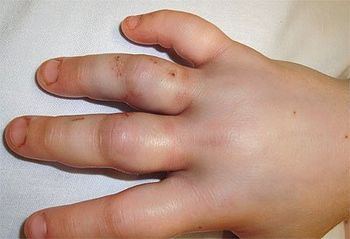

One week earlier, a 14-month-old girl with a history of eczema was evaluated because of a diffuse rash of excoriated lesions, some of them purulent. She was afebrile. Worsening eczema with secondary infection was diagnosed. Treatment with oral clindamycin was prescribed. At follow-up, the lesions had worsened. The child had multiple excoriated papules, some of which had coalesced into plaques. She also had two 5-mm vesicles on her right shoulder. Eczema herpeticum was diagnosed clinically. Culture of the vesicles later grew herpes simplex virus (HSV).